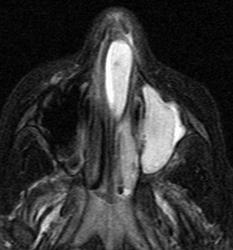

Кисты.